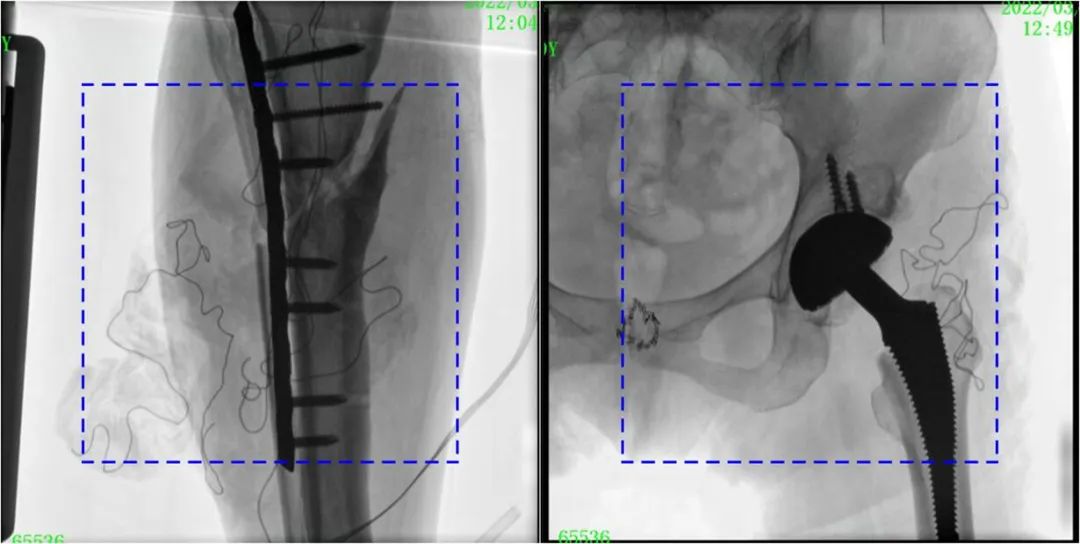

術(shù)中定位準確、出血量少,術(shù)后影像顯示股骨移位糾正,恢復良好力線,手術(shù)效果良好。

PLX119C臨床圖像與傳統(tǒng)圖像對比

注:藍色虛線內(nèi)為傳統(tǒng)21CM×21CM平板的成像區(qū)域。